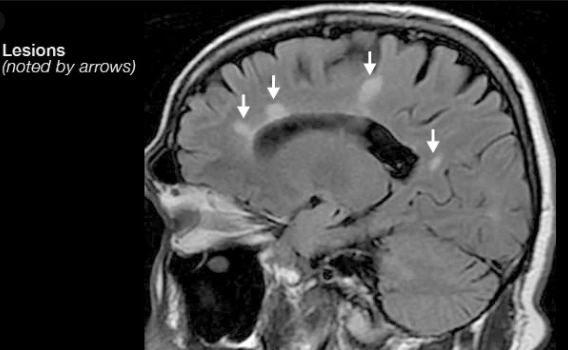

Which imaging modality is used to support a diagnosis of MS?

MRI - lesions look like smudges

Shows contrast-enhancing lesions in the white matter especially around the ventricles, brainstem and cerebellar peduncles